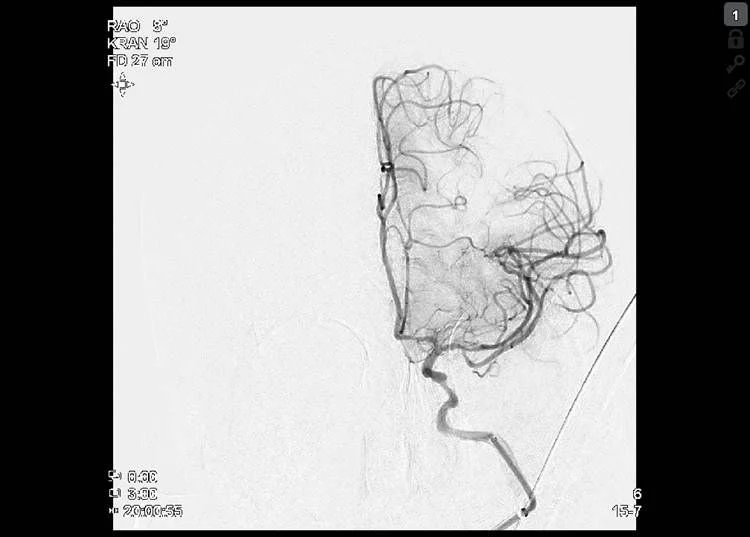

Stroke CT workup showed 16 ml well delignated infarct of the head of caudatenucleus and putamen (ASPECTS 8), a proximal left M1 occlusion and 40 ml of perfusion lesion in the MCA territory (18:25, Brainomix). No thrombolysis.

Thrombectomy was done with Embovac and Tigertriever (Rapid Medical) in general anaesthesia (door-to-groin 109 min, 19:44) with first pass recanalization TICI 2c in 16 min (20:00, door-to-final-TICI 123 min).